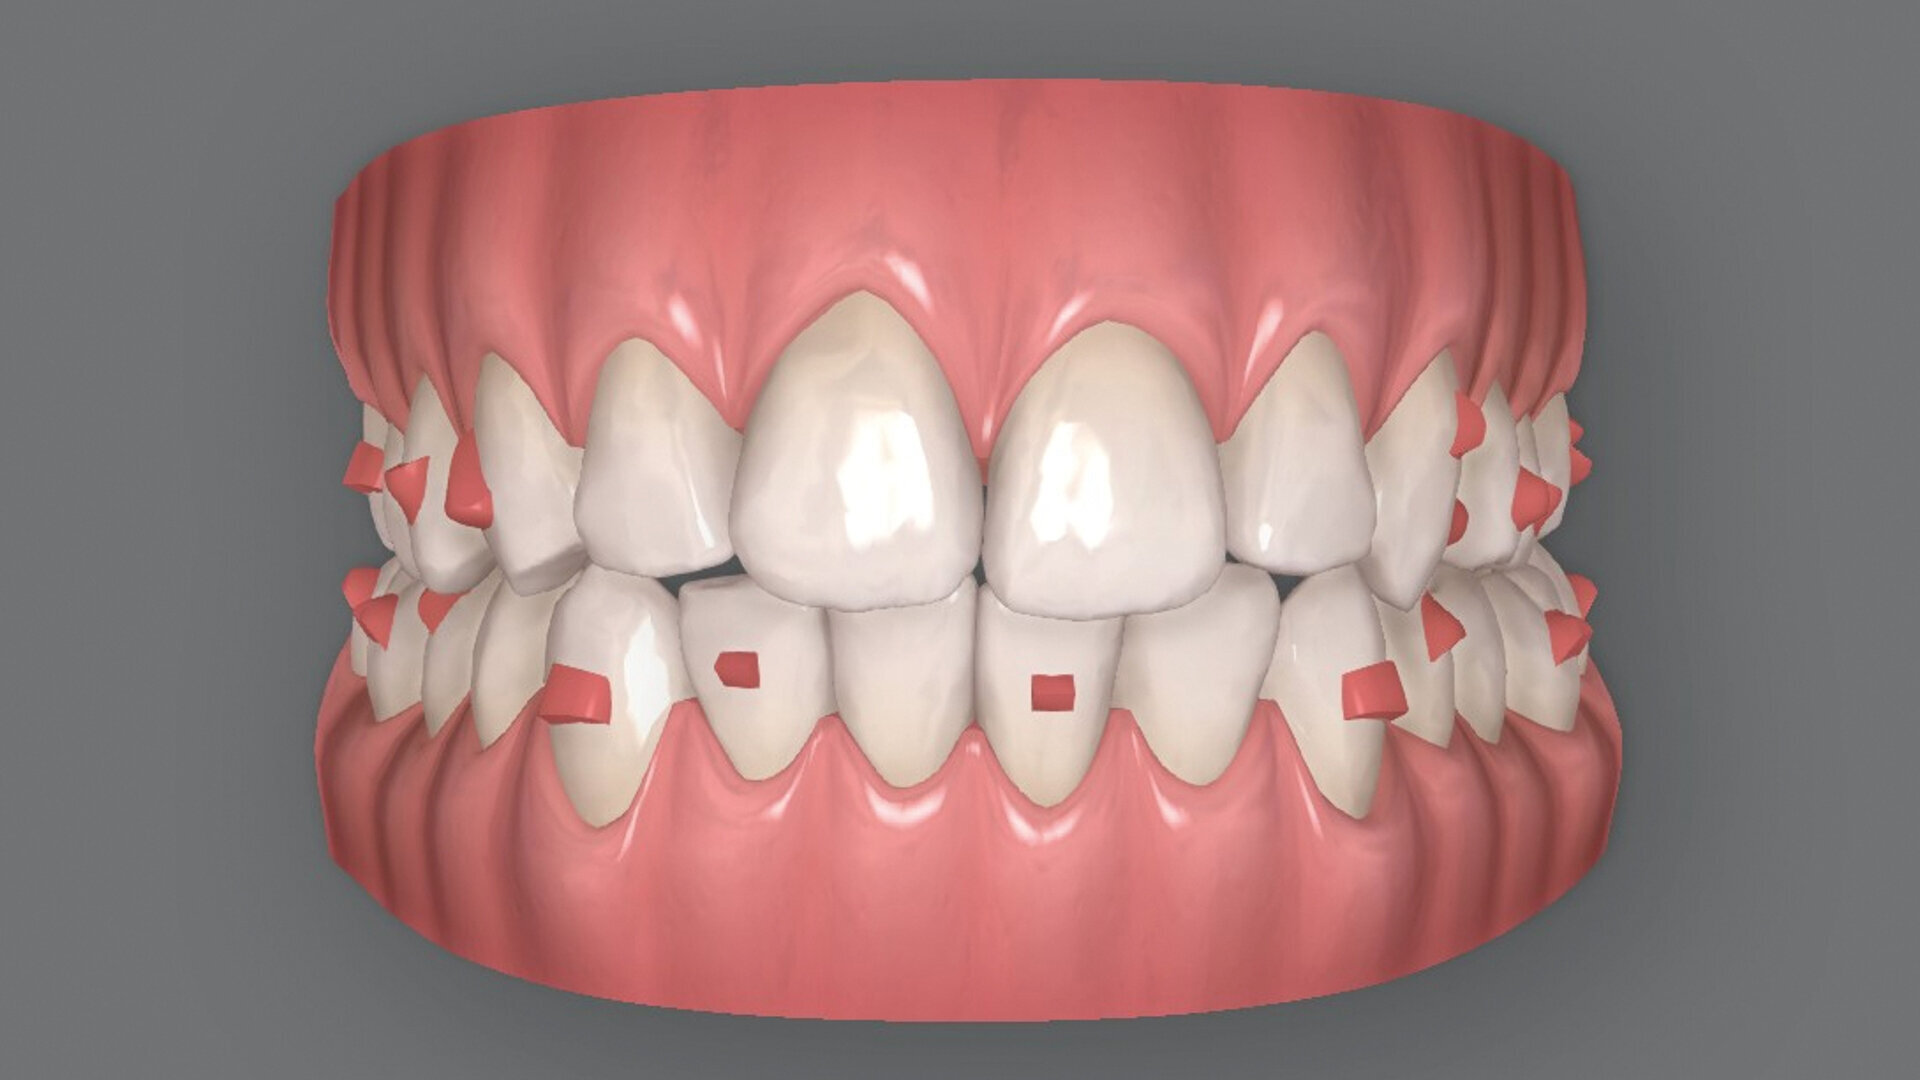

Le premier plan de traitement par simulation ClinCheck prévoit 53 aligneurs, afin de réaliser une distalisation séquentielle postérieure d’environ 4 mm sur le côté gauche du maxillaire, une expansion de 2 mm par quadrant et un alignement dans la zone antérieure. Il prévoit également une réduction interproximale (RIP) sélective de 0,25 mm sur chaque face des dents de l’arcade mandibulaire, et de 0,10 mm à 0,15 mm pour les dents de l’hémiarcade maxillaire droite (Fig. 4). Une application topique de fluorure est planifiée dans les zones soumises à une RIP après la procédure. Des élastiques de classe II sont utilisés du côté gauche pour faciliter la distalisation. La fréquence de changement des aligneurs est fixée à sept jours et elle sera ramenée à cinq jours par la suite. Un accélérateur de traitement orthodontique par vibrations est utilisé, afin d’augmenter la vitesse et la prédictibilité des mouvements dentaires. Le traitement n’envisage pas l’utilisation d’aligneurs de surcorrection.

La première série d’aligneurs permet de réaliser les mouvements orthodontiques programmés dans le logiciel avec une efficacité supérieure à 95 % (Fig. 5), et d’obtenir une forme anatomique des arcades, une correction de l’occlusion croisée et de la relation de classe II du côté gauche, une réduction de l’encombrement dans le maxillaire et la mandibule, et un alignement des lignes médianes. Au terme de cette première phase, les observations cliniques indiquent une infraclusion postérieure, résultant de l’intrusion passive des dents postérieures due à l’épaisseur du matériau de l’aligneur, et des contacts antérieurs prématurés. Quelques mouvements dans la zone incisive mandibulaire sont encore nécessaires pour terminer le traitement, et un deuxième jeu d’aligneurs est donc prévu pour éliminer les problèmes et finaliser la position des dents.

Le deuxième plan ClinCheck consiste en 16 aligneurs maxillaires et mandibulaires afin d’effectuer une extrusion des dents postérieures maxillaires et mandibulaires, ainsi qu’une rétraction des incisives mandibulaires de façon à alléger les contacts et fermer l’infraclusion dans la région postérieure. L’accélérateur de traitement par vibrations est toujours utilisé quotidiennement, et l’intervalle de changement des aligneurs est fixé à cinq jours, puis à trois jours par la suite. Les derniers aligneurs ne sont portés que 12 heures par jour afin de permettre la fermeture passive finale de l’infraocclusion postérieure.